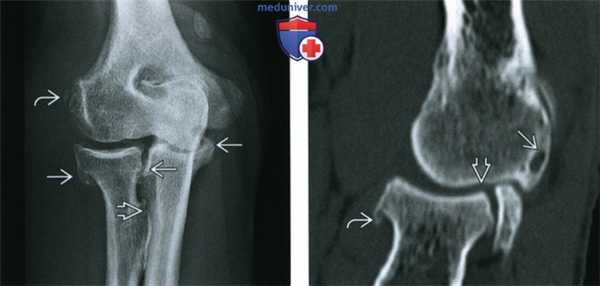

Проще всего и с высокой точностью диагностировать артроз позволяет рентген-снимок. На нем будут видны признаки, характерные для той или иной стадии заболевания:

- 1 стадия. На снимке еще не видны костные разрастания, но поверхность сустава неровная, иногда со слегка окостеневшими участками. Суставная щель незначительно сужена, поэтому внешние симптомы пока не выражены.

- 2 стадия. Уже хорошо заметны костные разрастания, щель – примерно в 2-3 раза уже нормы. Специалист отмечает субхондральный склероз – один из признаков артроза, уплотнение и разрастание костной ткани.

- 3 стадия. На снимке вообще не видна суставная щель. Большая часть суставной поверхности закостенела, увеличилась за счет краевых разрастаний. Один из признаков – «суставная мышь», перемещение осколка мениска, хряща или кости, что кардинально ограничивает двигательную активность.

Только рентген позволяет точно установить степень артроза